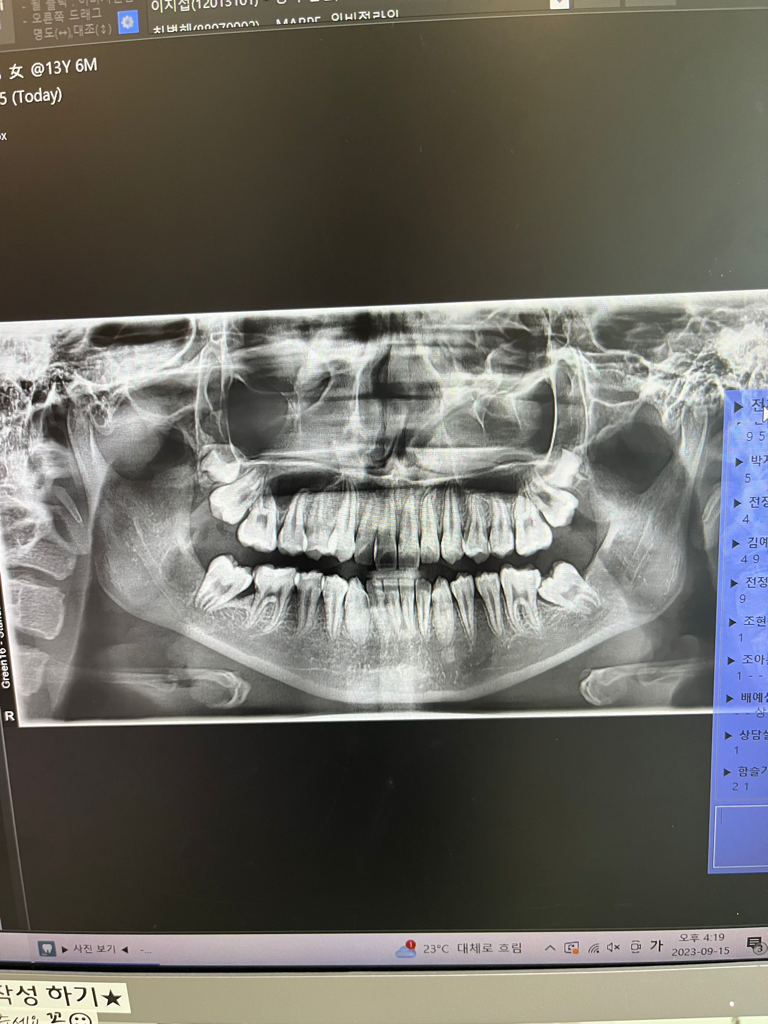

중1딸아이 치아엑스레인데 전체교정 필요할까요??

전 어금니 누운것만 하고싶은데

• 2번 째 사진

엑스레이만 가지고는 사실 교정 진단을 하기는 힘듭니다만 간단히 봤을 때에는 전체 교정이 필요해 보입니다.

정확한 분석을 위해서는 좀더 진단이 필요하지만 올린 x ray 사진만 보아도 전체 교정을 해야 할 것으로 보이며 부분교정은 아무 드물게 사용합니다.

누워잇는 치아를 끌어 올리기 위해서는 공간확보가 필요한데 아마 전체 교정을 해야될 가능성이 높아 보입니다. 교정 진단을 해봐야 알겟지만, 단순히 저 치아만 올리는건 쉽지 않아 보이네요.